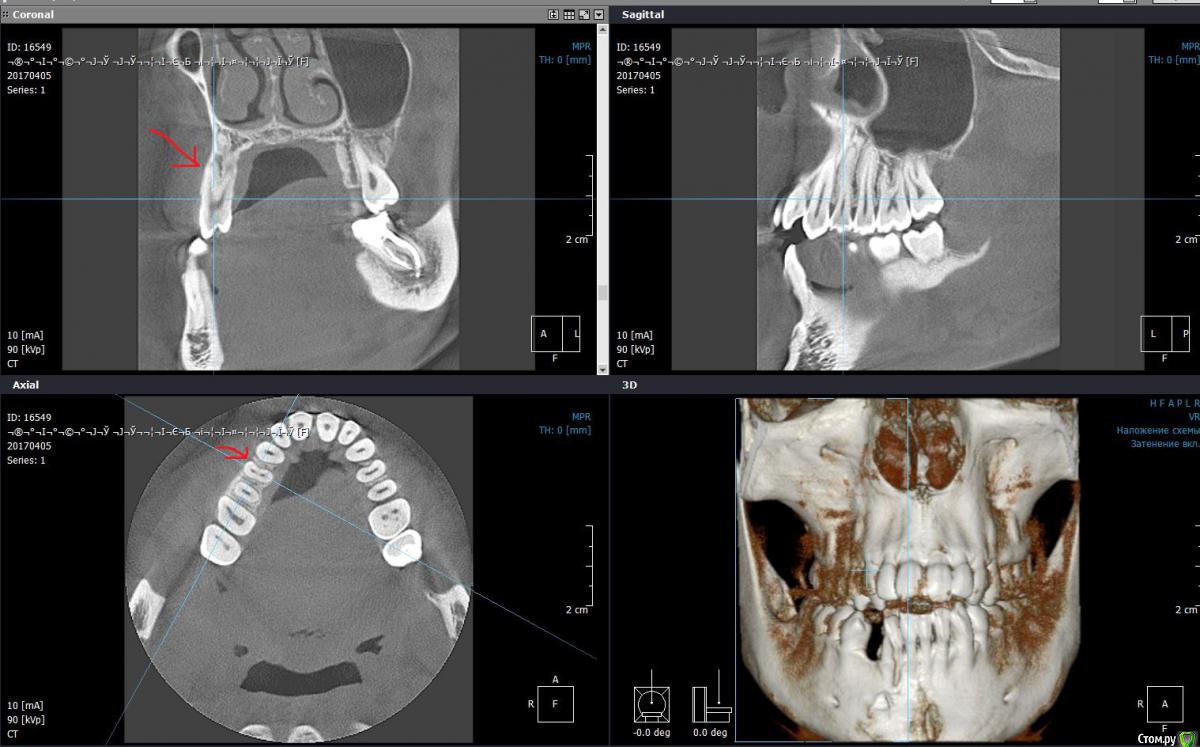

Monkey Опубликовано 25 августа, 2017 Поделиться Опубликовано 25 августа, 2017 (изменено) Коллеги, очень нужен совет. пациентке 20 лет. Как вы расширяете зубной ряд в похожих ситуация? На каких дугах? Какая активация, как часто? Стоит ли пробовать кросс-эластики? И реально ли избежать резорбции кортикалки? Изменено 25 августа, 2017 пользователем Monkey Ссылка на комментарий

Opdihatop Опубликовано 25 августа, 2017 Поделиться Опубликовано 25 августа, 2017 В таких случаях стараюсь убедить на SARPE. Если не выходит, то нивелирую инклинацию и делаю послабление небного шва и RME. По идее лучше всего делать MARPE, но личного опыта в этой методике пока не приобрел. Режим активации зависит от выбранной методики. 1 Ссылка на комментарий

Yana guapa Опубликовано 25 августа, 2017 Поделиться Опубликовано 25 августа, 2017 мой похожий кейс закончился сарпе и члх..... ну и самолиги в помощь в любой ситуации, где ходите добиться бОльшего ремоделирования кости. 1 Ссылка на комментарий